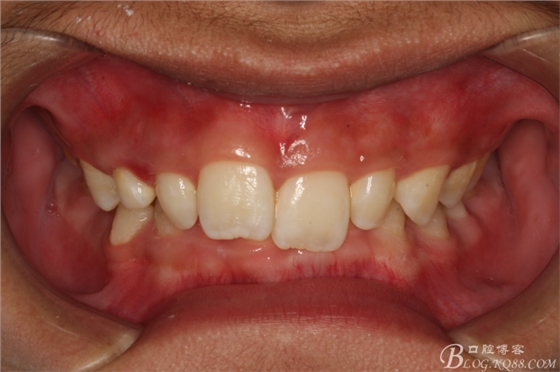

圖2.右側(cè)位咬合影像:乳尖牙滯留